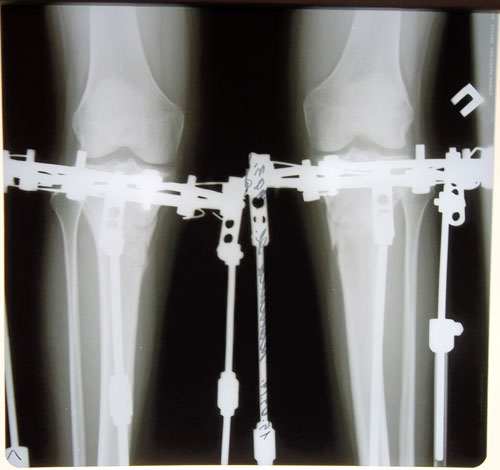

ДО 02.07.2014г.

Дата операции 02.07.2014г.

Дата снятия аппаратов 15.09.2014г.

Срок лечения 73 дня.